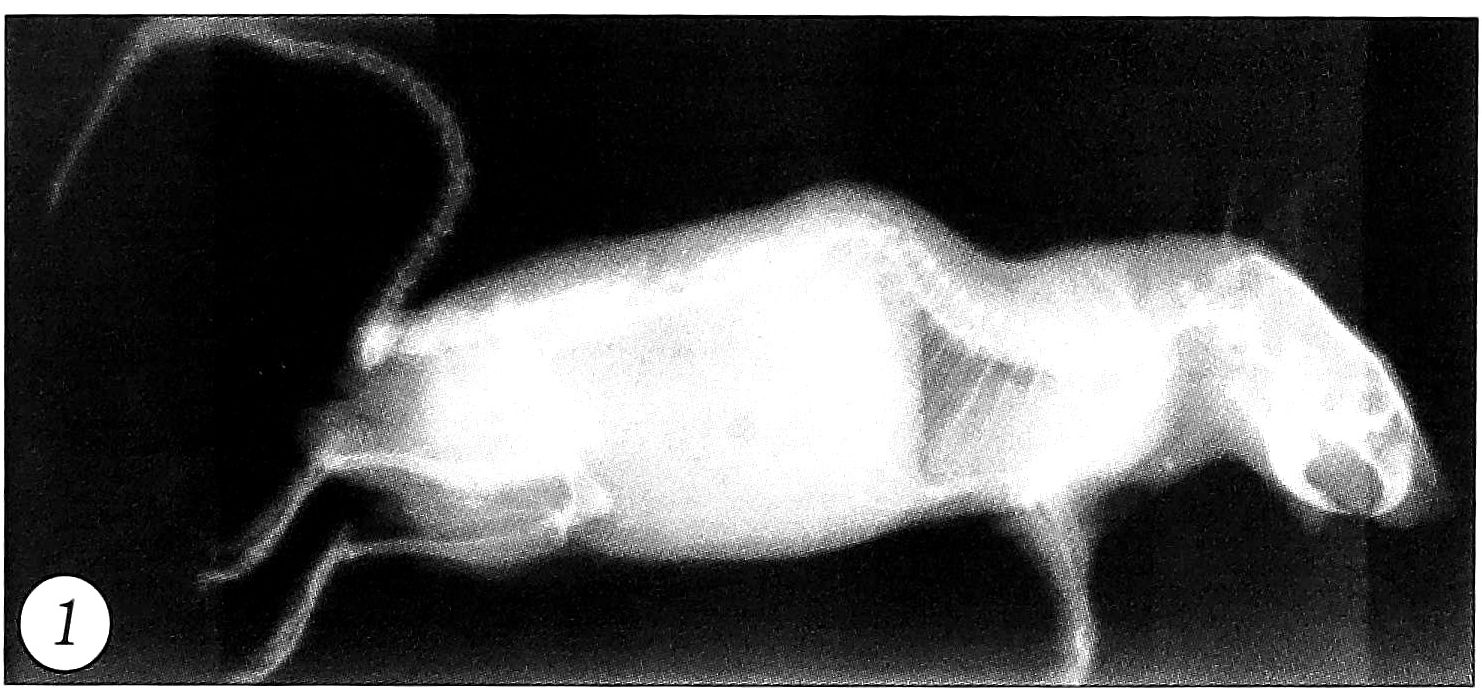

Клинико-рентгенологическое исследование. Через 1,5 мес у подопытных животных наблюдалась клинически определяемая кифотическая деформация грудного отдела позвоночника. Рентгенологически отмечалась деформация в 40° по Коббу с вершиной кифоза на уровне грудопоясничного отдела позвоночника (рис. 1). На вершине искривления выявлялись клиновидно измененные тела позвонков.

Рис. 1. Кифотическая деформация позвоночника у подопытной 1,5-месячной мыши.

У двух особей в поясничном отделе позвоночника присутствовал и сколиотический компонент.

В 3-месячном возрасте деформация позвоночника у животных становилась ригидной. Угол кифоза на уровне Т4-6 позвонков достигал 60°. Тела позвонков на вершине искривления были клиновидно изменены, межпозвонковые диски неравномерно сужены. На уровне Т5 позвонка имелись грыжи Шморля.

Через 6 мес кифотическая деформация в среднегрудном отделе позвоночника усугублялась. Угол кифоза достигал 70-90°, наблюдались клиновидные изменения тел позвонков (рис. 2). На вершине дуги деформации выявлялись грыжи Шморля.

Рис. 2. Кифотическая деформация позвоночника у подопытной 6-месячной мыши.